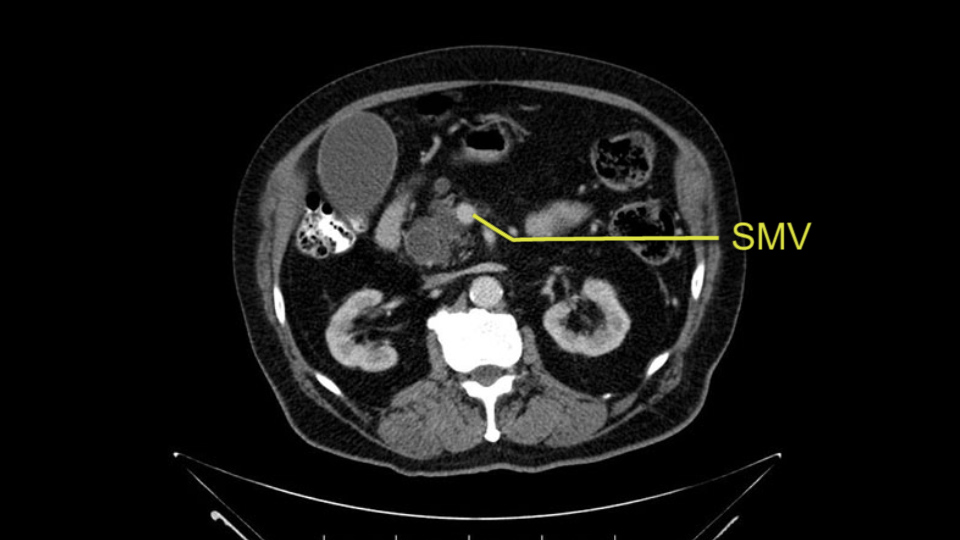

The next item that I would look at: the issue would be the vessels and usually start at the portal vein, watch the portal vein, follow it down, down-down-down to the neck of the pancreas - which is here - and there’s no impingement by tumor, which is great. The SMV and the splenic vein, which is here. The splenic vein junction is normal, which is great.

Then look at the first jejunal branch - which is this thing here - this little branch which goes under the SMA. It’s something that we’ve just started appreciating over the past few years and the reason for that is: there’s two or three small branches that come out of the uncinate into the the first jejunal and it’s a fairly inevitable part of the operation where there’s some bleeding. As long as you’re cognizant of what’s happening, it’s no reason to panic and that kind of bleeding will eventually stop or can be stopped but it’s not easy because these little vessels are fragile from the uncinate to the first jejunal. So I do focus on that and it’s pretty consistent I’d say 9 times out of 10, people have that first jejunal.

The other thing I look at is the gastroepeiploic arcade- which is this thing here- which is where the gastroepeiploic vein joins the portal vein. I call it the gateway to the neck of the pancreas because you pretty much have to divide it to get to the neck. The middle colic vein usually drains either into it or nearby. I think we’re seeing it here. Again,that can be divided and I usually divide those two and it helps me get under the neck. Again, there’s no issues here with the tumor so it’s nice from that perspective. If I was concerned about the vein, which I’m not here, I would go to the coronal view. It’s a nice way to look at the vein on just a couple of cuts and you can see a beautiful view of it here. There’s the portal vein, there’s the head of the pancreas. There’s the tumor. It’s a little closer here than it looks on the other one. I doubt it’s involved. If it’s touching, it may not be invading it but even if it was, it's a short segment. Anyways, there’s the SMV there’s the splenic vein, and everything looks good. You can see the stent. I ignore the stent. It’s the most dramatic looking thing in the picture but it’s actually the least important.

Then either through the coronal or the axial, I’ll do both. Look at the SMA -which is here- I had already looked at it and I don’t see any involvement. There’s the SMA with a nice fat plane between the SMA and the tumor. Over here you can see on the axial, there’s the SMA. Everything on the right side of the SMA has got some nice black around it, which is fat, which means probably no tumor [no tumor, no tumor]. Follow it up to the origin, coming off the aorta. So those are the two technical things that I worry about: the SMA and the SMV.

The initial hepatic flexure mobilization and the Kocher procedure is then going to enable me to understand the uncinate process of this patient, which should not be a problem, again. But the initial pictures had shown a degree of touching. I would not even say involvement or abutment; a degree of touching with the superior mesenteric vein. So that would give me an early chance to assess how the superior mesenteric vein is in this patient. So this would be the initial slowing down moment.

The next thing we always evaluate, although we do not expect invasion to the portal veins in this case, we must always trace the path of the portal vein, in both directions, from top to bottom. The splenoportal confluence and the superior mesenteric vein, which in this case does not appear to be compromised.

The first steps of a pancreaticoduodenectomy involve ensuring the CT findings are correct: exploring for signs of metastatic disease, peritoneal implants involving the omentum or the undersurface of the diaphragm and if again this is confirmed exploration that there's no metastatic disease, I begin the mobilization and really determining the relationship of the tumor with the major visceral vessels. I start by an extended Kocher maneuver, identify the superior mesenteric vein below the neck of the pancreas. They’re very thin walled vessels and as you're dissecting you have to use the ultimate care and meticulously dissect the superior mesenteric vein, ligate the anterior branches and begin the dissection from below to under the neck of the pancreas. At this point, if there's no reason to be concerned about whether there is any vascular invasion below, I usually take the gallbladder down. I mobilize the common hepatic duct above the insertion of the gallbladder. This patients already has a stent in place. So I would divide the bile duct at this point. This facilitates the dissection of the anterior surface of the portal vein and as I would expect looking at this imaging that there is nothing to be concerned about in terms of vascular involvement.